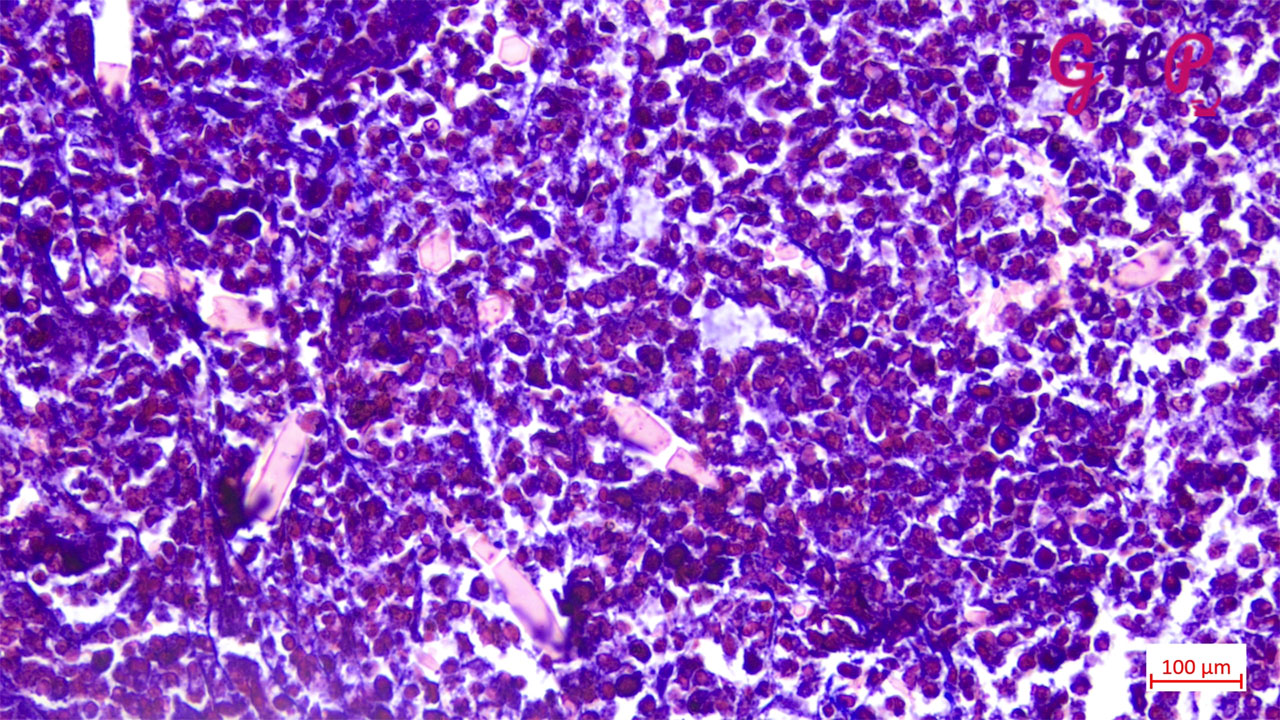

Microscopic Images-

Microscopic examination showed eosinophilic abscess with multiple cholesterol clefts.

PAS, MT and Orcein stains performed showed presence of CharcotLayden crystals.

Visceral larva migrans (VLM) is a parasitic (roundworm) infestation caused by Toxocaracanis and Toxocaracati of the genus Toxocara.Liver biopsy is characterized by eosinophilic granulomas and the presence of Charcot-Leyden crystals, which are formed from the breakdown of eosinophils.